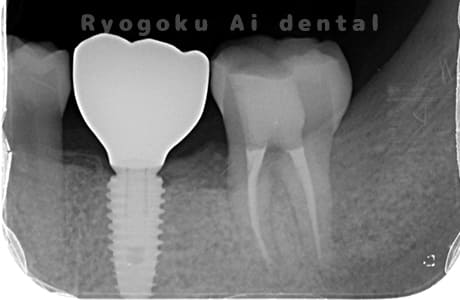

Case10

-

術前

術後

- 原因

- 左下6番欠損

- 治療内容

- インプラント治療

- 治療費用

- 約600,000円

左下の奥歯に歯を入れて欲しいとのことでご来院された患者様です。インプラント治療が最適とご提案させて頂き、治療を行いました。経過も良好で、大変満足して頂けました。

<リスク・副作用>

治療後、痛みや違和感、出血、腫れなどが出る事があります。喫煙者、糖尿病などの方の場合、歯が生着しない場合があります。